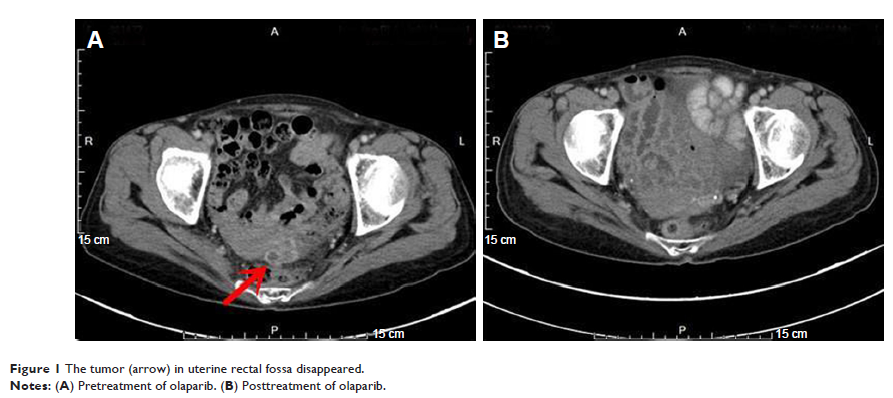

Case Report

- 作者:Yuan Cheng, Juan Zhang, Shu kui Qin, Hai qing Hua

- 期刊:OncoTargets and Therapy